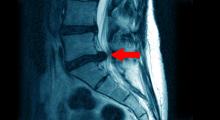

Bandscheibenvorfall: Röntgenaufnahme

Zur Diagnose eines Bandscheibenvorfalls werden verschiedene Untersuchungen und Abklärungen durchgeführt. Dazu gehören unter anderem:

• Ausführliche Anamnese (Krankengeschichte) unter Einbezug der Symptome

• Körperliche Untersuchung

• Neurologische Tests (Nerventests)

• Computertomographie

• Magnetresonanztomographie (MRT)